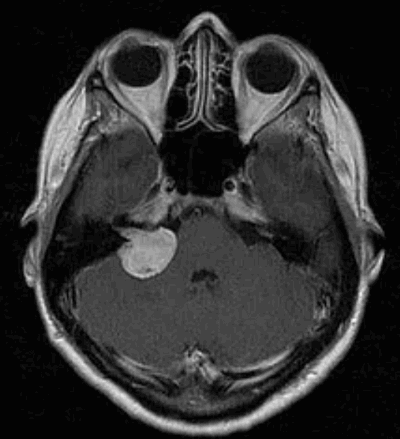

Диагностика

Наиболее информативным методом выявления вестибулярных шванном является МРТ головного мозга с контрастным усилением в режиме Т1 и Т2. Это исследование позволяет определить размеры опухоли, наличие перитуморозного отека, наличие признаков окклюзионной гидроцефалии, которая может быть следствием сдавления опухолью IV желудочка. Кроме этого МРТ позволяет провести дифференциальную диагностику с другими опухолями схожей локализации (чаще с менингиомой задней грани пирамиды височной кости). Еще одним стандартом диагностики является КТ в костном режиме. Независимо от снижения слуха стандартом является проведение аппаратной аудиографии.